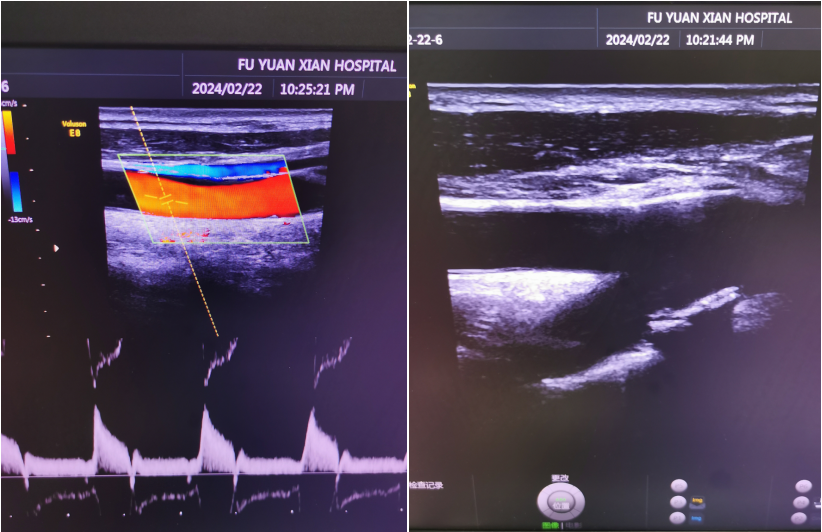

大家通常看到的以黑、白、灰为主色调的超声检查就是我们的二维超声,也称之为B型超声或者是灰阶超声,它是各种超声检查的基础,它能够实时、动态显示出脏器和组织的形态、大小及解剖结构。在超声扫查中,不同层次的灰色即我们报告中所呈现的强回声、高回声、低回声及无回声等将不同脏器和组织的解剖结构清晰地显示到屏幕上。部分医生习惯于将其转换成其它色彩来观察,我们称之为伪彩,也就是大部分患者所认为的彩色超声。

而真正的彩超指的是,彩色多普勒超声,是在二维超声的基础上,利用多普勒原理对检查部位的血流信息进行处理,直观地将血管中的血流信号以红、蓝等彩色来表示,并叠加在二维灰阶图像上实时地显示出来,能更好地显示组织内血流分布情况,并可判断血流方向、显示平均流速信息。